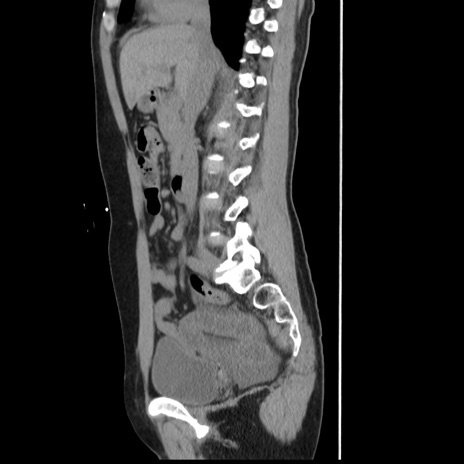

症例10(矢状断像)

【症例】 50歳代女性

【主訴】 腹痛

【現病歴】前日生レバーを食べた。今朝に排便あり。 昼前に突然発症の腹痛を生じ、当院救急外来を受診した。

【既往歴】 子宮筋腫にてで子宮全摘後

【身体所見】 意識清明、腹部:平坦、軟、下腹部やや左を中心に圧痛・反跳痛あり、筋性防御あり

【データ】WBC 7800、CRP 0.07